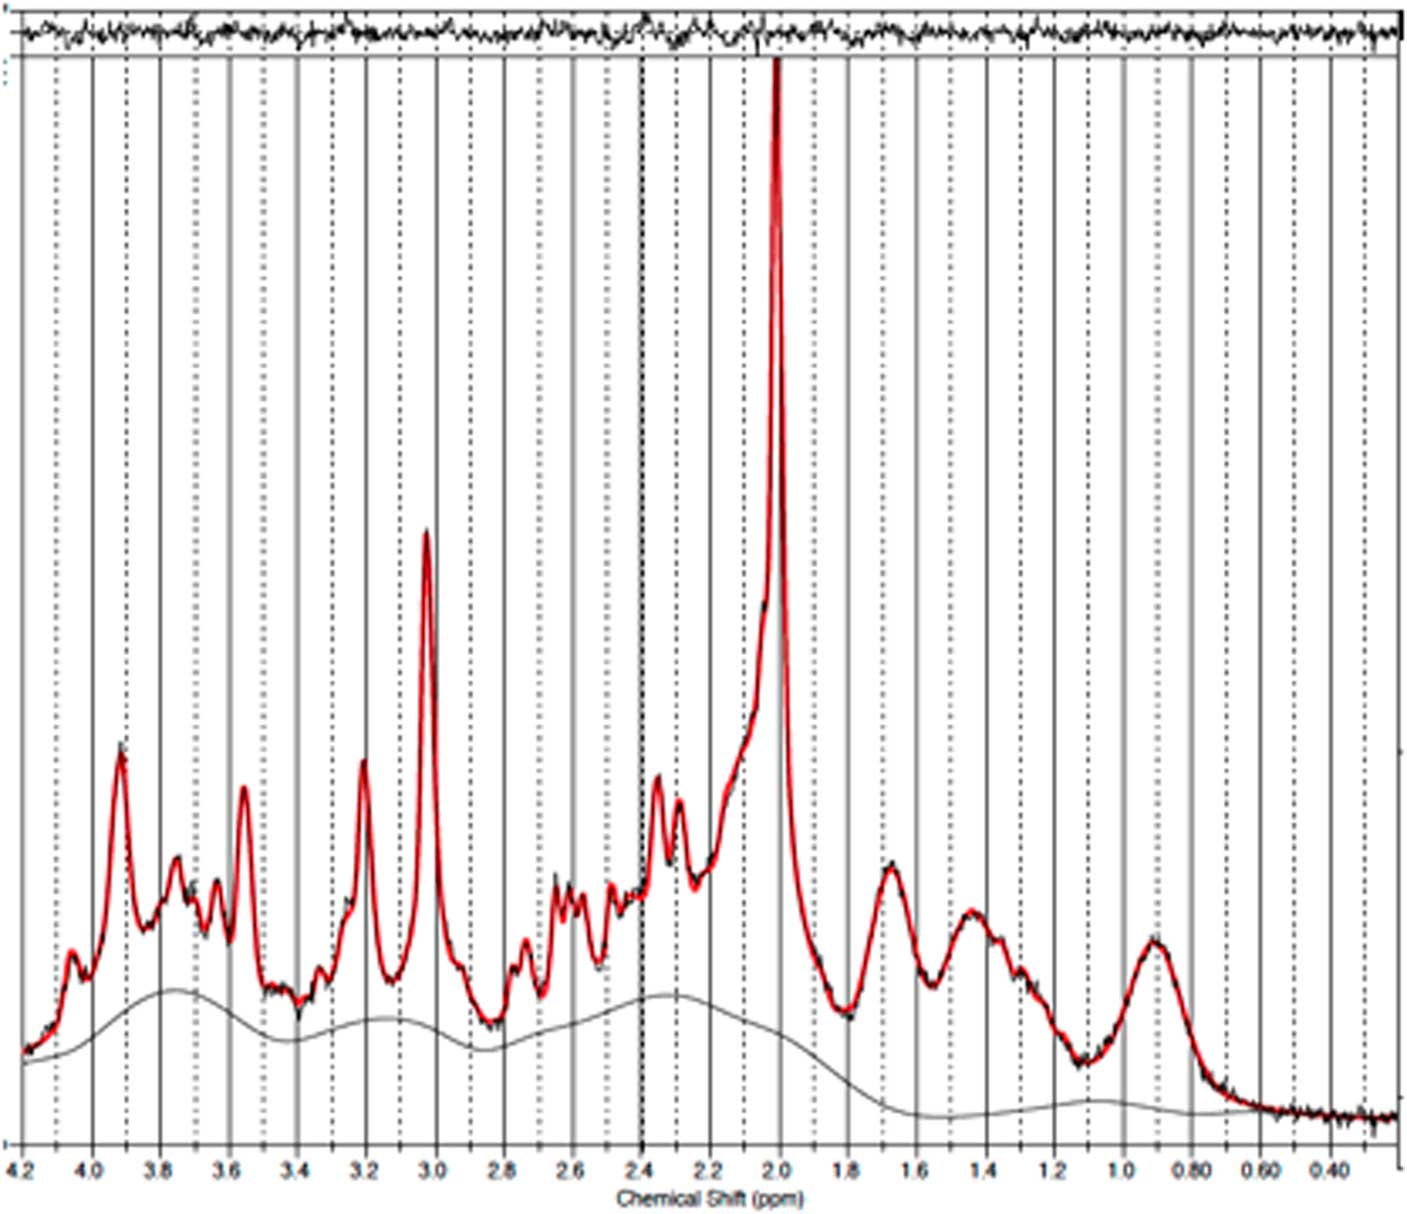

Baseline and follow-up data were collected from all 11 patients. However, prefrontal spectra from one patient (male) and one healthy subject (male) were discarded due to poor quality (CRLB>20%). Figure 2 illustrates representative spectra from PFC and Fig. 3 an individual plot for the GABA signal in PFC. No significant difference in prefrontal GABA levels was observed between patients pre-ECT (mean 0.248±0.04) and healthy subjects (mean 0.249±0.03), t(20)=0.089, p=0.93 (Fig. 4). To examine whether GABA/Cr ratios were affected by changes in creatine, we tested for significant differences in GABA/NAA ratios (p=0.92) and NAA/Cr ratios (p=0.99), but no significant difference was found. Diagnosis, that is bipolar disorder or MDD did not interact significantly with the GABA/Cr ratio (p=0.75). Moreover, we found no significant changes in GABA/Cr ratio after excluding patients receiving benzodiazepines.

Fig. 2 Example of a representative spectrum from the prefrontal cortex. The raw data are plotted as a thin black curve. The thick red curve is the LcModel fit to this data. The baseline is also plotted as a thin black curve. At the top are plotted the residuals.

Magnetic resonance analysis

All spectra were processed in MATLAB Version R2013b using the FID-A processing toolkit (Reference Simpson, Devenyi, Jezzard, Hennessy and Near23) where subspectra were aligned, motion-corrupted averages were removed, frequency and phase drift-correction was performed and zero- and first-order phase corrections were applied. Processed SPECIAL data were then analysed using LCModel version 6.3-1H (Reference Provencher24), which models the data as a linear combination of 21 simulated basis spectra (alanine, asparate, phosphocholine, creatine, phospocreatine, gamme-aminobutric acid, Gln, Glu, GSH, glycine, myo-inositol, lactate, NAA, scyllo-inositol, taurine, beta-hydroxybutyrate, glucose, N-acetylaspartyl glutamate, glycero-phosphocholine, phosphoethanolamine, serine). The LCModel analysis was performed on spectra for chemical shifts in the range of 0.2–4.2 ppm. All metabolite concentrations were calculated in reference to total creatine (creatine+phosphocreatine). The GABA/Cr ratio was the primary outcome measure whereas other metabolites such as GSH/Cr, NAA/Cr, Glu/Cr, Cho/Cr and Gln/Cr were secondary outcomes. The quality of the spectra was assessed using spectral linewidth, signal-to-noise ratio and the standard error estimate for the model fit of each peak called the Cramér–Rao lower bounds (CRLB). Concentration estimates with CRLB>20% were removed from further analysis. Moreover, spectra with linewidths greater than 8 Hz or with Signal-to-noise ratio lower than 40 were discarded. Spectral linewidth was defined as the full width at half maximum and is a function of B0 field homogeneity over the measured volume of interest. The signal-to-noise ratio was defined as the maximum spectrum minus the baseline over the analyse window (i.e. between 0.2 and 4.2 ppm) divided by the standard deviation of residuals. The LCModel software reported all three measures.